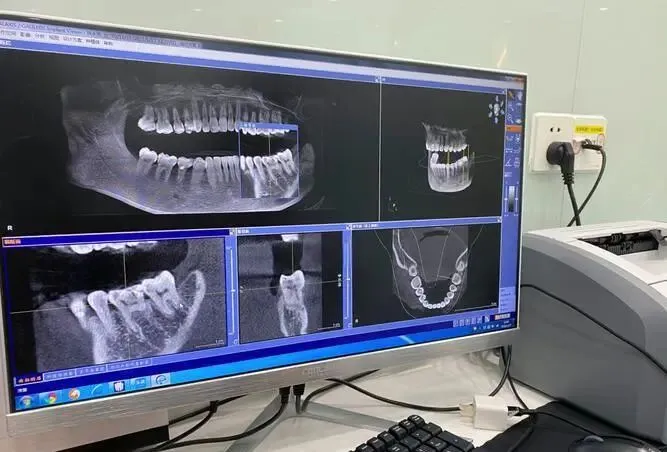

• 医生建议优先:专业医生会根据您的CT影像评估骨质、骨量,推荐最适合的品牌